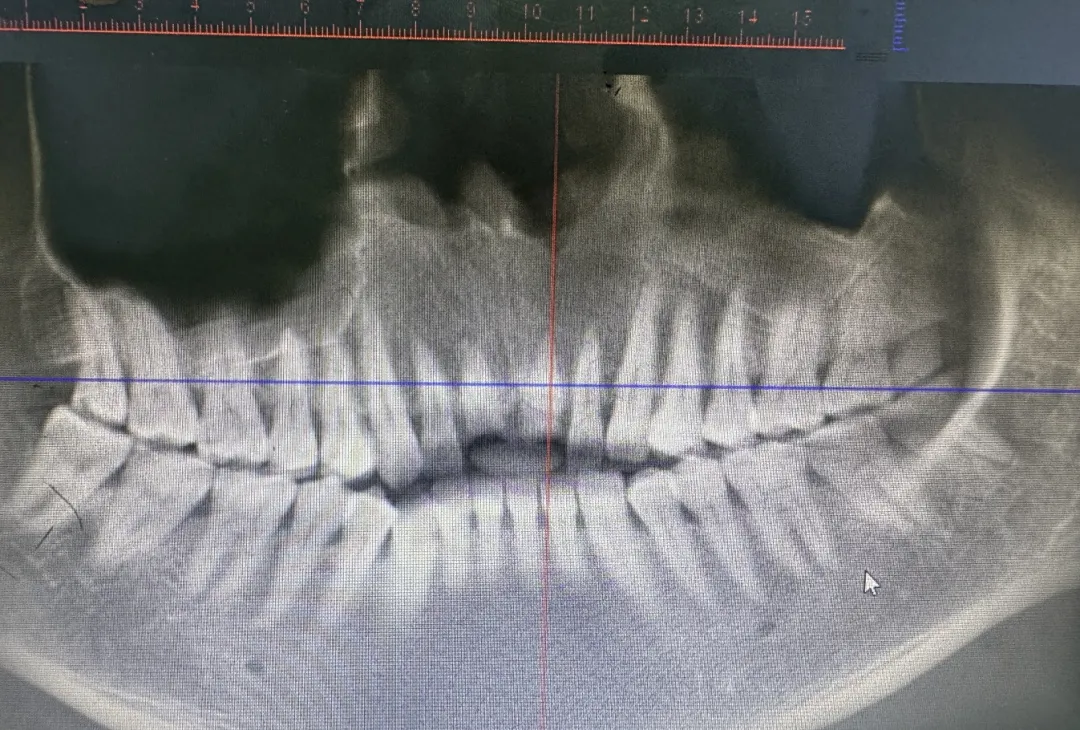

拍片检查

经过详细拍片检查发现

一颗牙断裂到了牙龈处

另一颗剩在牙龈里裂成三节

“这两颗牙都保不住了”

建议拔除后进行微创即刻种植